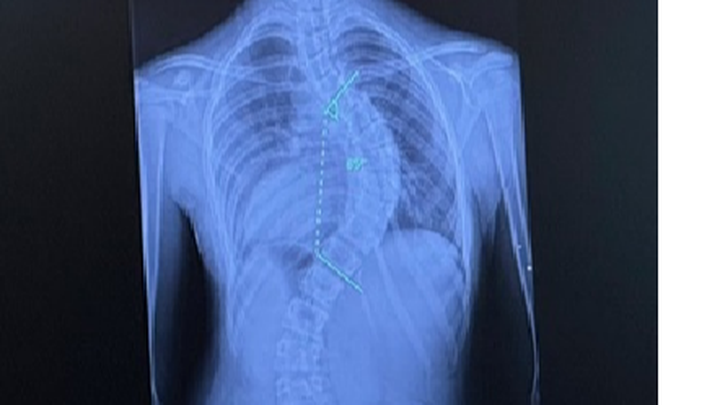

Hello! I am Rebeckah Finchum, and I am trying to help raise money for my granddaughter to have scoliosis surgery with rods in her back. Her mother has to pay the majority of the money upfront to cover the deductible on her insurance policy. She will also have to be in the hospital post-surgery for about a month to recover and do physical therapy to help heal and strengthen her back.